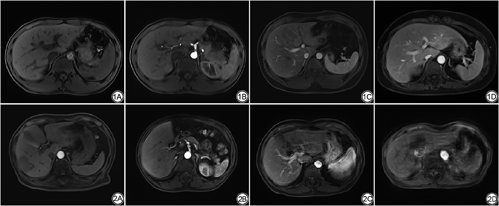

所有图像均使用Siemens Syngo工作站进行分析。为保证盲法评估的客观性,由两位分别具有6年和13年影像诊断经验的影像科主治医师分别对三组图像进行评价,包括动脉期图像的期相评价、图像质量评价,并最终讨论达成一致意见。二者的评价方法均采用四分法。动脉期期相评分标准(图1)如下:1分为肝动脉中无对比剂;2分为动脉早期(仅肝动脉有对比剂,但门静脉和肝实质无增强);3分为动脉晚期(肝动脉和轻度门静脉增强,无明显肝脏实质增强或肝静脉增强);4分为门静脉期(肝实质和肝静脉增强)。动脉期图像=动脉早期+晚期图像,动脉早期捕获率=动脉早期例数/总例数,动脉晚期捕获率=动脉晚期例数/总例数。

主观图像质量从图像伪影、肝脏边缘清晰度及病灶显示三个方面评价(图2):1分为无伪影,肝脏边缘及病灶清晰可见;2分为轻度伪影,边缘轻度模糊不影响诊断;3分为中度伪影,边缘中度模糊能够诊断;4分为重度伪影,边缘重度模糊无法诊断。客观图像质量评估图像的SNR与CNR,三组动脉期图像的肝实质及同层面的右侧竖脊肌内放置感兴趣区(region of interest, ROI)。ROI的放置标准如下:(1)以门静脉为中心连续三个层面肝脏和竖脊肌相同的位置;(2)均要避开血管、胆管、占位病变、脂肪间隙和伪影区;(3)尽可能确保每个放置的位置相同,大小相等且尽可能大。将相应的测量结果取平均值得到肝脏和竖脊肌的信号强度(signal intensity, SI)及竖脊肌的信号强度标准差(standard deviation, SD)。计算公式如下:SNR=SI肝脏/SD竖脊肌;CNR=(SI肝脏-SI竖脊肌)/SD竖脊肌。CDT-VIBE组取五期图像SNR与CNR的平均值。SNR与CNR由上述高年资影像科医师测量并计算。